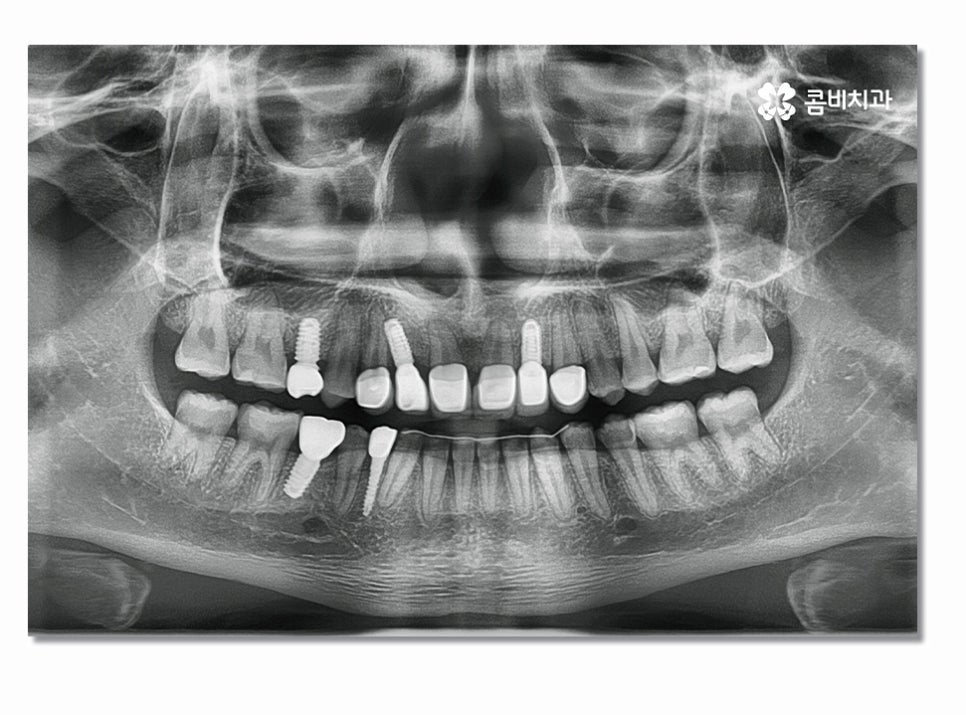

많지만 오늘 사례는 청결관리 미흡과 불규칙한 치열로

인해서 충치가 심해졌고 결국 발치 후 앞니 임플란트까지

하게 된 사례를 함께 살펴보실 거예요.

위 환자분의 경우에는 심미적으로 중요한 앞니를

잃기도 했지만 불규칙한 치열과 평소 청결관리 및 식습관의

문제가 있었고 비교적 젊은 나이에 영구치를

상실하고 이런 원인을 개선하기 위해

교정치료를 함께 병행한 케이스라고 할 수 있어요.

앞니임플란트의 경우 어금니에 비해 시술 난이도가

높은 편인데 심미적인 부분도 중요하며 임플란트의

식립 각도, 윗니와 아랫니의 교합에 대한 이해도,

잇몸 상태, 인접 치아와 자연스러운 결과 등

다각도로 판단해야 하기 때문에 의료진의 경험과

3D CT 등을 활용한 정확한 검진이 중요하다고 할 수 있어요.

특히 위 환자분의 경우에는 앞니 올 세라믹 치료와

치아교정, 임플란트를 동시에 진행해야 했기 때문에

전체적인 조화와 치료 계획을 철저하게 세울 필요가 있었고